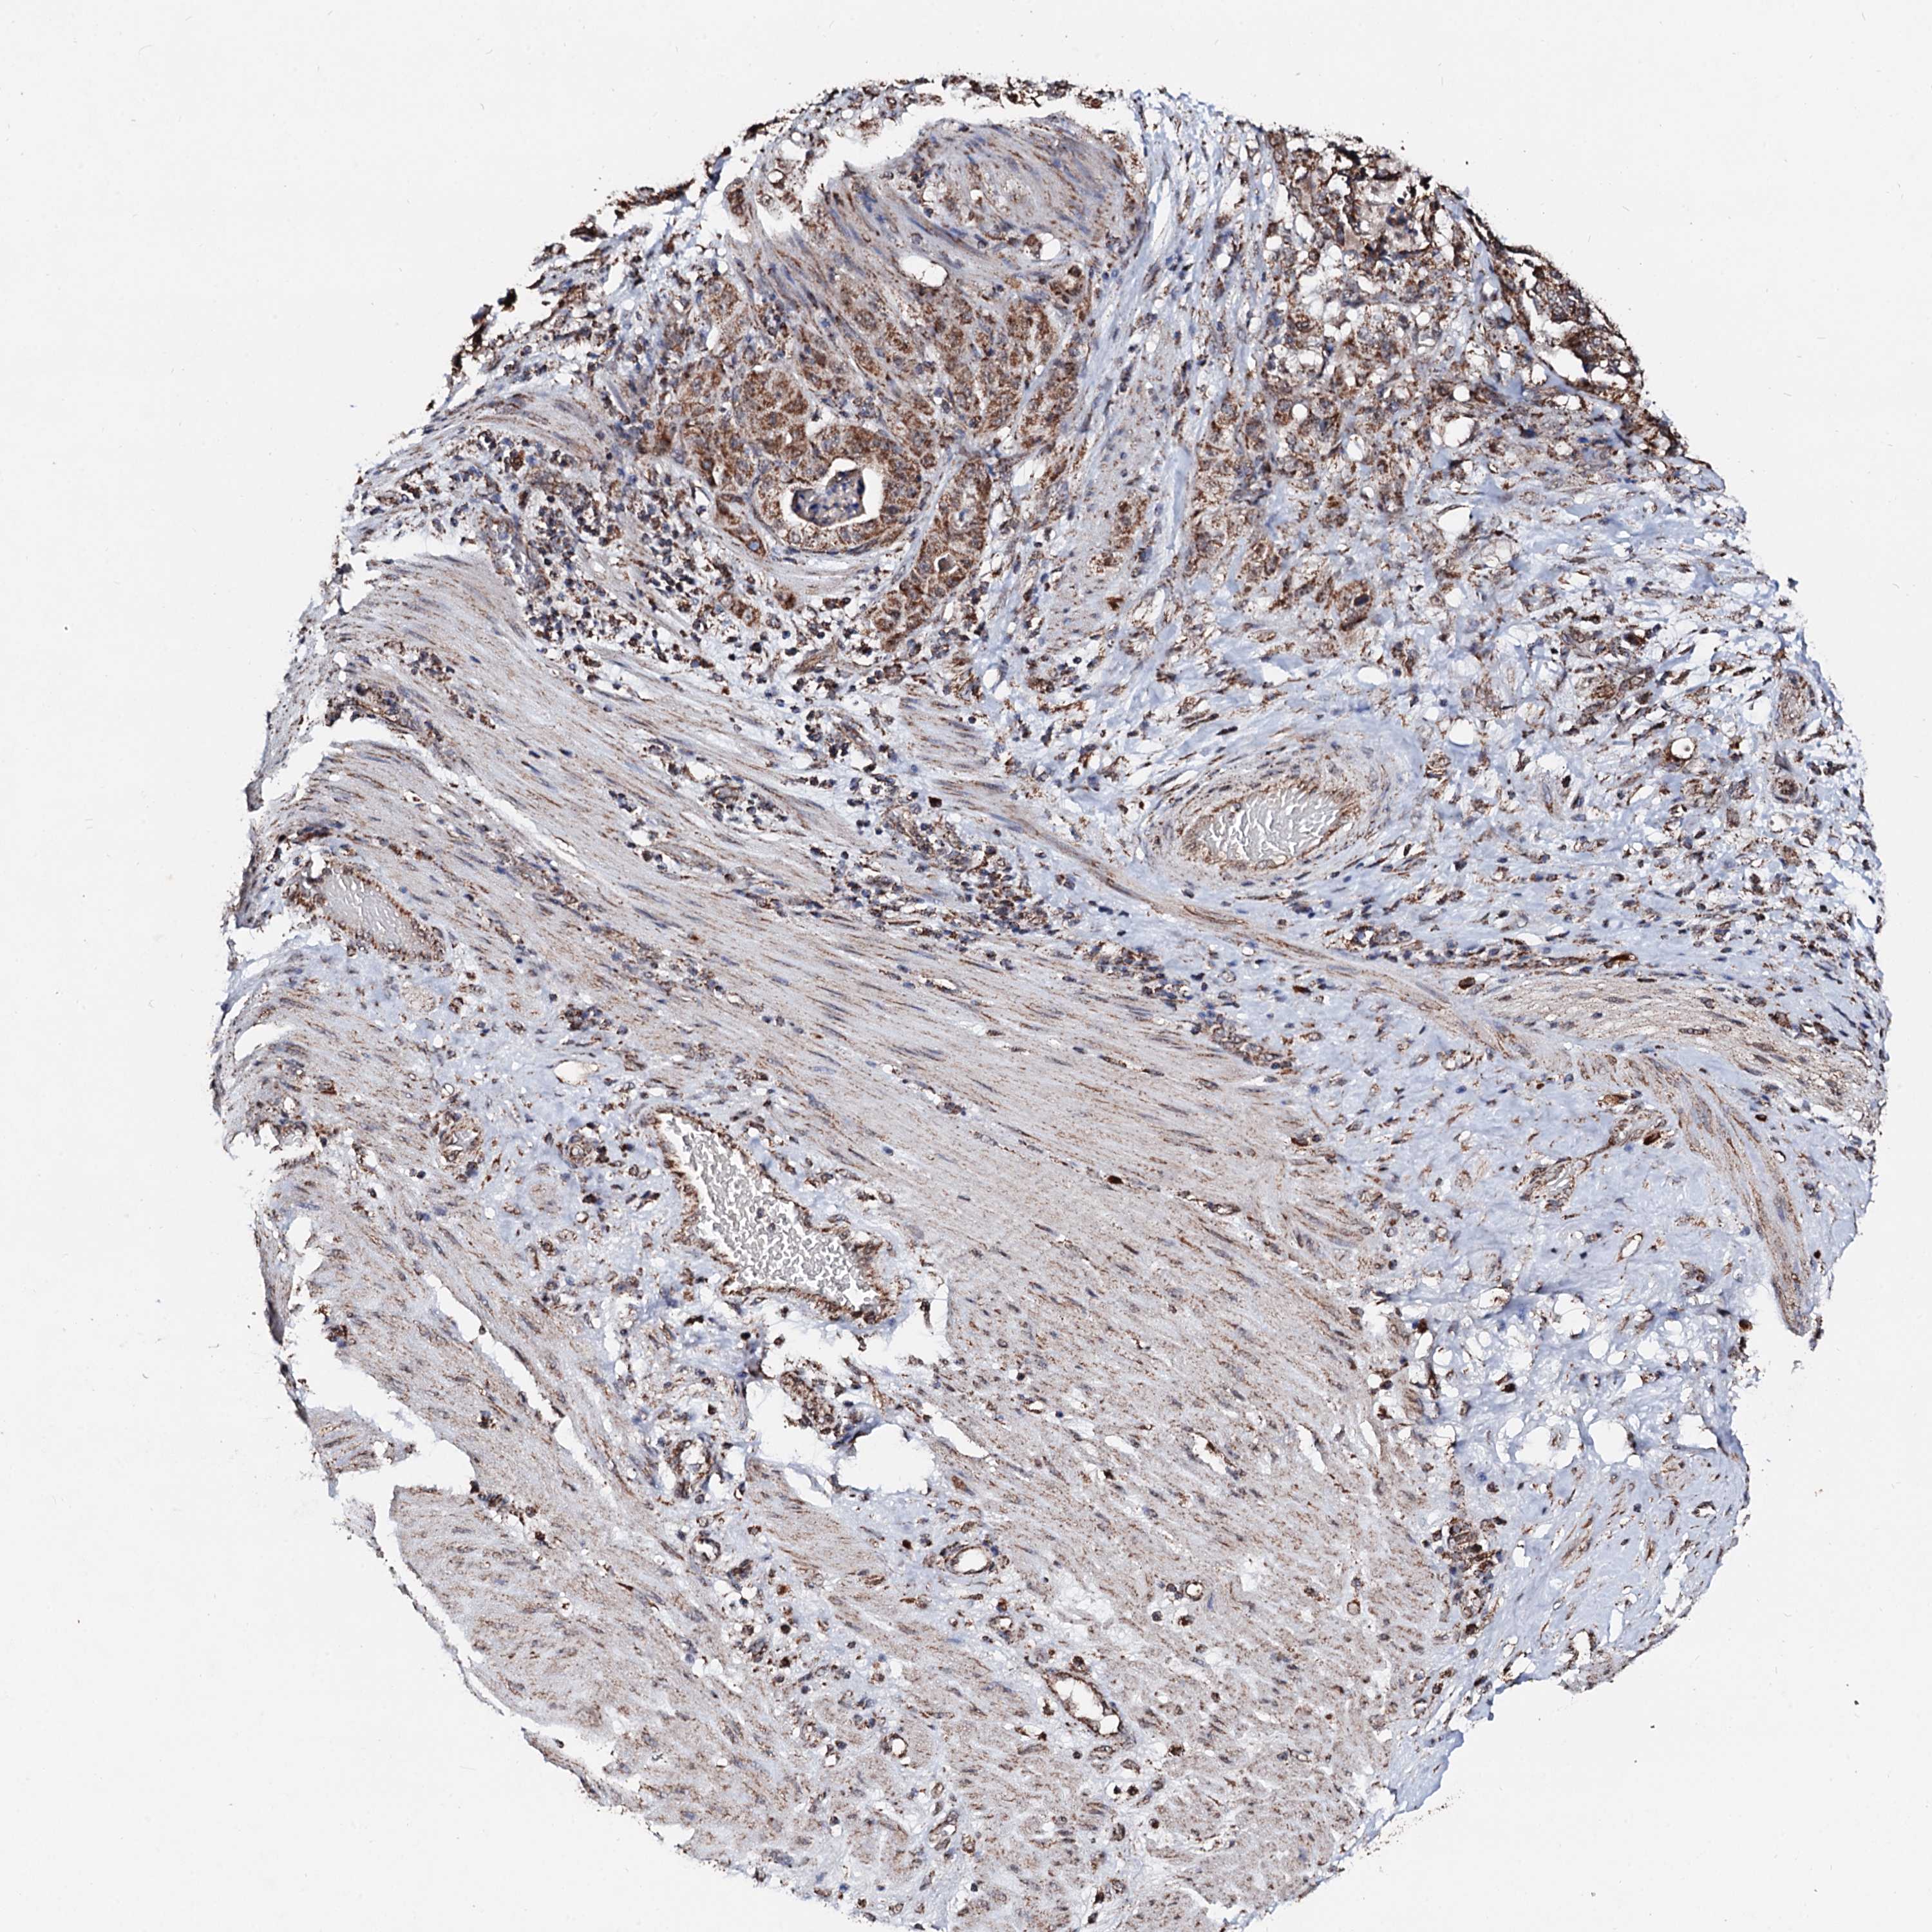

STOMACH CANCER - Protein expressioni

A mouse-over function shows sample information and annotation data. Click on an image to view it in a full screen mode. Samples can be filtered based on level of antibody staining by selecting one or several of the following categories: high, medium, low and not detected. The assay and annotation is described here.

Note that samples used for immunohistochemistry by the Human Protein Atlas do not correspond to samples in the TCGA dataset.

Antibody stainingi

Antibody staining in the annotated cell types in the current human tissue is reported as not detected, low, medium, or high, based on conventional immunohistochemistry profiling in selected tissues. This score is based on the combination of the staining intensity and fraction of stained cells.

Each image is clickable and will lead to virtual microscopy that enables deeper exploration of all samples and also displays staining intensity scores, fraction scores and subcellular localization as well as patient and tissue information for each sample.

Antibody HPA039875

Staining

High

Medium

Low

Not detected

Intensity

Strong

Moderate

Weak

Negative

Quantity

>75%

75%-25%

<25%

None

Location

Nuclear

Cytoplasmic/membranous

Cytoplasmic/membranous,nuclear

Adenocarcinoma, NOS